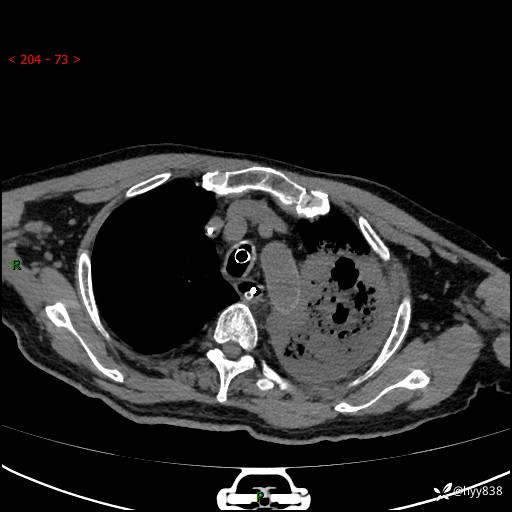

胸部CT平扫(2024.7.24)